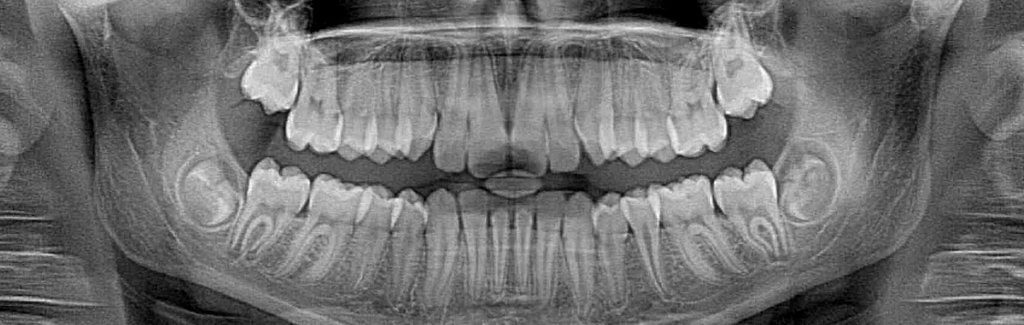

Dental X-rays enable dentists to see decay inside teeth that would not be visible to the naked eye. This allows us to act earlier against cavities, which is much better for the teeth. However, X-rays do expose patients to radiation, which is why you always wear a lead apron when the images are being taken. Thanks to advances in technology, there is now a safer way to take these images.

Film X-rays have been used in dentistry for decades. In the past few years, many forward-thinking dentists like Dr. Thoms have invested in digital X-ray technology. Film X-rays cost a bit less than digital X-rays but the increased exposure to film X-rays is more harmful to a patient’s overall health. Our digital X-ray emits as much as 85 percent less radiation than traditional X-ray technology.

Digital X-rays are one of the most important new advances in our office. We are not only able to reduce your exposure to radiation but also increase the diagnostic proficiency. In addition to increased diagnostics, we reduce the amount of harmful chemicals and other waste materials associated with traditional X-ray technology. The reduction in waste was a big consideration when deciding to invest in digital technology. We pride ourselves in being environmentally responsible.